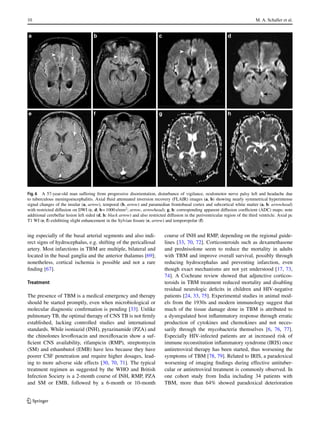

Fig. 6 A 57-year-old man suffering from progressive disorientation, disturbance of vigilance, oculomotor nerve palsy left and headache due

to tuberculous meningoencephalitis. Axial fluid attenuated inversion recovery (FLAIR) images (a, b) showing nearly symmetrical hyperintense

signal changes of the insular (a, arrow), temporal (b, arrow) and paramedian frontobasal cortex and subcortical white matter (a, b: arrowhead)

with restricted diffusion on DWI (c, d; b= 1000s/mm2

; arrow, arrowhead); g, h: corresponding apparent diffusion coefficient (ADC) maps; note

additional cerebellar lesion left sided (d, h: black arrow) and also restricted diffusion in the periventricular region of the third ventricle. Axial pc

T1 WI (e, f) exhibiting slight enhancement in the Sylvian fissure (e, arrow) and temporopolar (f)